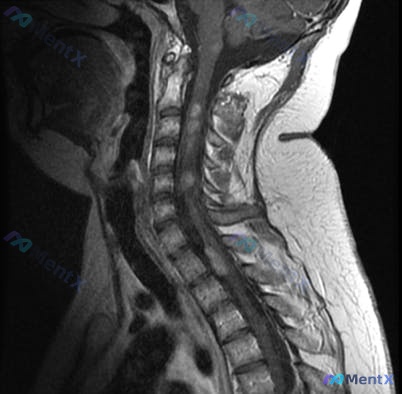

整理了一个很有意思的病例,第一眼很容易被常见病带偏。 基本情况:32岁女性 病史:6年前确诊双侧前庭神经鞘瘤,持续性面部感觉异常、听力损伤;无常规用药。 本次表现:上肢疼痛、无力,痛温觉减退(导致被热水烫伤)。 查体:双上肢肌力3/5,双上肢远端痛温觉分离。 影像:颈椎MRI提示生理曲度变直,C4/...